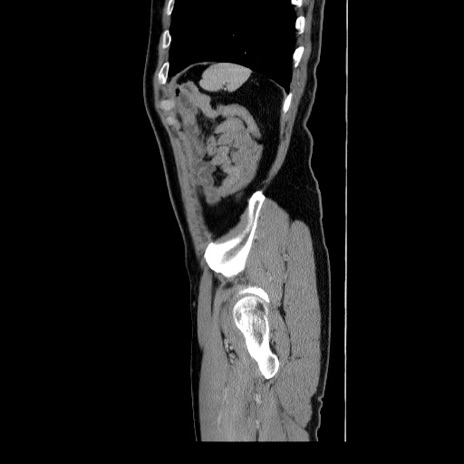

症例34(矢状断像)

【症例】60歳代 男性

【主訴】右鼠径部膨隆

【現病歴】1年程前より右鼠径部膨隆あり。自己にて還納可能だったため放置していた。3時間前より右鼠径部の脱出を認め、還納困難となり受診。

【身体所見】右鼠径部に小児頭大の膨隆あり。弾性硬であり、用手還納は困難。左鼠径部にも膨隆を認める。脱出はなし。